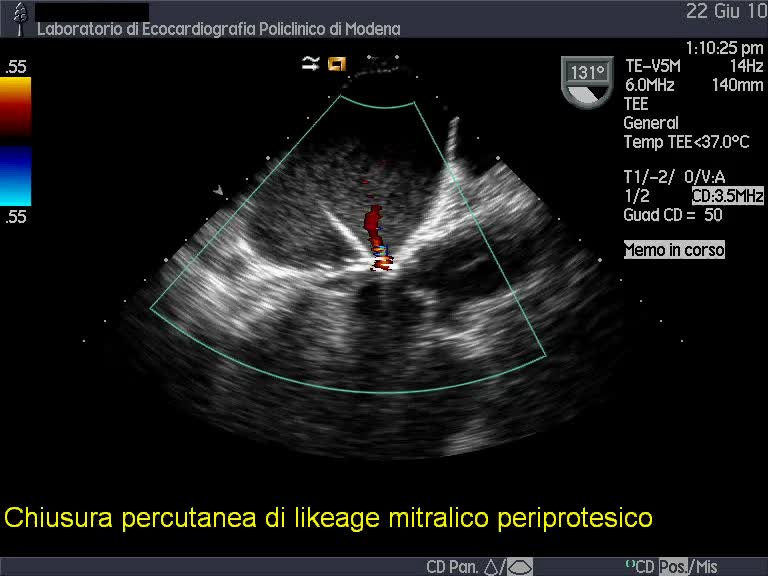

Chiusura percutanea di paraleak (protesi valvolare mitralica biologica)

Chiusura percutanea di paraleak (protesi valvolare mitralica biologica)Autore: Andrea Barbieri

Categoria: Videoalbum

Parole chiave: catetere ecotee3d im interventistica intraoperatorio leak -